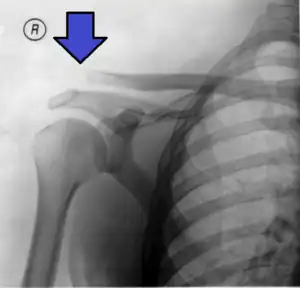

Type 3 -

Type 3 AC joint separation on plain X ray

This is a more severe form of a type III injury, with the trapezial and deltoid fascia stripped off of the acromion as well as the clavicle. This is type III but with exaggeration of the vertical displacement of the clavicle from the scapula. Distinguishing between Type III and Type V separations based on radiographs is difficult and often unreliable between surgeons.[19] Type V is manifested by a 2- to 3-fold increase in the coracoclavicular distance.[13] The shoulder manifests as a severe droop, secondary to downward displacement of the scapula and humerus due to loss of the clavicular strut.[13]